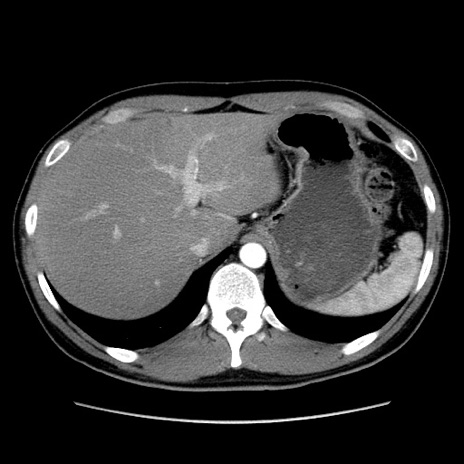

症例36(横断像)

【症例】20歳代 男性

【主訴】心窩部痛

【現病歴】今朝より上腹部痛あり。一旦軽快していたが再度出現したため救急要請。昨日夕に白身の魚を含む刺身を食べた。

【身体所見】BP 136/89mmHg、HR 74/min、BT 37.0℃、腹部:膨満、軟、心窩部に圧痛あり。反跳痛なし、筋性防御なし、腸雑音やや亢進あり。

【データ】WBC 17700、CRP 0.48